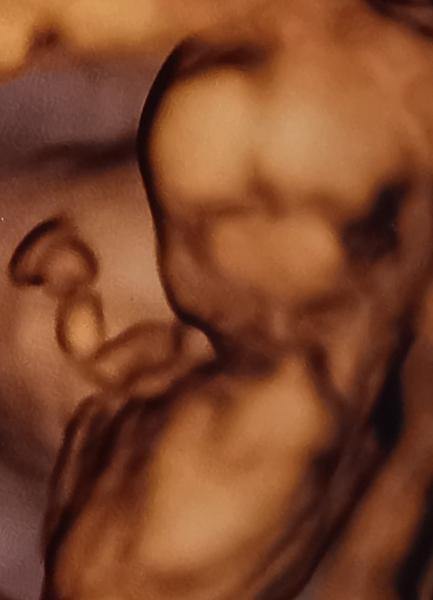

Heute eröffne ich mal unseren Dickbauchdienstag. 😁 Von mir gibt es aber immer noch kein Bauchbild, dafür aber eins von meinem Bauchbewohner. ​​​​​​ Wir waren letzte Woche bei der frühen Feindiagnostik, es war soweit alles okay. Keine Fehlbildungen ersichtlich, da fiel uns echt ein Stein vom Herzen. 🍀 Krümel ist da schon 8cm groß gewesen, wog schon fast 100g und war insgesamt eine Woche "weiter" bzw. in allen Messwerten entsprechend größer. Da war ich bei 13+1 und ich bin mir auch sicher, dass das rechnerisch auch korrekt so ist. Wir haben meinen Zyklus sehr genau getrackt und zum potenziell früheren Befruchtungszeitraum gar nicht geherzelt. Wir haben wohl also einfach nur ein schnell wachsendes Baby. ☺️ Die Nackenfalte war auch normal mit 2mm. Das Nasenbein war allerdings nicht richtig darstellbar, da unser Krümel sein Gesicht nur schräg zeigen wollte und hat stattdessen lieber mit der Plazenta gekuschelt. 😍 In der 21. Woche sollen wir nochmal zur abschließenden Feindiagnostik, wo Gehirn und Herz sich nochmal genauer angeschaut wird. Auch die konkreten Fehlbildungen, die wir unbedingt ausschließen lassen wollten (familiäre Vorgeschichte), werden da nochmal 100% ausgeschlossen. Morgen bin ich endlich 14+0 und wir erfahren das Geschlecht vom NIPT-Test. Wir sind schon ganz gespannt. 🤗 Und in zwei Wochen habe ich Termin für den ersten Zuckertest plus normale Vorsorge mit erneutem Ultraschall.    Was gibt es bei euch so neues? Macht jemand von euch Schwangeren-Yoga oder plant es zumindest? Gibt es wieder anstehende Ultraschalluntersuchungen diese Woche?